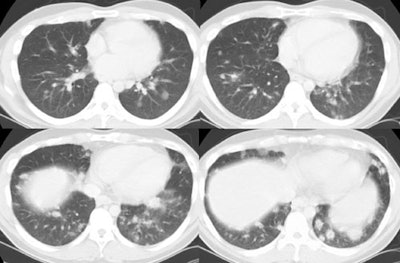

The patient below presented with complaints of cough, malaise, and a low-grade fever. The chest radiograph revealed some patchy left lower lobe airspace disease and vague nodular shadows- particularly in the lower lung zones. A chest CT was performed and demonstrated multiple nodular airspace abnormalities with variable margins. The lesions did not improve despite antibiotic therapy and all cultures were negative. Click images to enlarge. |